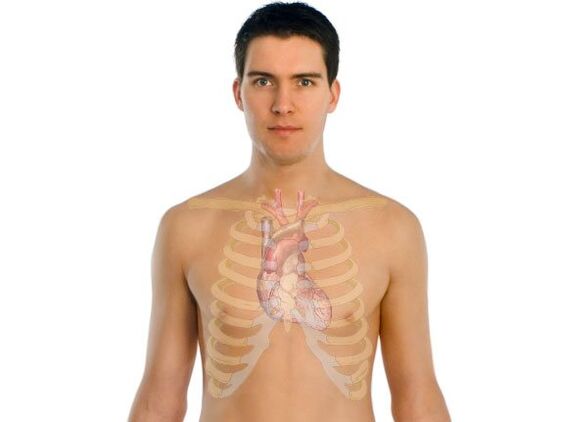

البكتيريا الطفيلية في جسم الإنسان، في أي أعضاء يمكن أن تعيش؟

تسمى الطفيليات التي تعيش على الجسم بالطفيليات الخارجية. يشمل هذا النوع البق والقمل ومسببات أمراض الجرب المماثلة. ويطلق على البعض الآخر اسم الطفيليات الداخلية لأنها تعيش داخل جسم الإنسان. وتشمل هذه الأميبا والديدان ويرقات الحشرات.

في أغلب الأحيان، يمكن العثور على الطفيليات الداخلية في الأمعاء والعضلات والدم والرئتين والقلب والكبد. حتى أن بعض الأنواع تعيش في الأنسجة العصبية. تعيش الطفيليات خارج الرحم على الجلد.